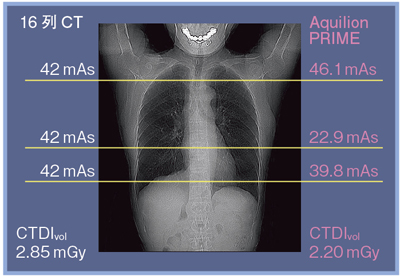

胸部のCT 第4版 | 村田喜代史, 上甲 剛, 村山貞之, 酒井文和 |本。胸部のCT 第4版 | 村田喜代史, 上甲 剛, 村山貞之, 酒井文和 |本。CC3 胸部CTの読影 - YouTube。kokuu 雑穀米 ホワイトブレンド グルテンフリー 2袋。CANON社製新型CT装置を導入 | 新柴又駅前クリニック(脳神経外科)。腹部CTを読影する上で重要な脂肪ウインドウとは? - YouTube。胸部CTの読影の基礎【働くのに必要な知識を最短で習得する方法。胸部CT画像の読影を支援するEIRL Chest CTの販売を開始 - エル。見逃しを防ぐための腹部CTの読影の順番|ごろ〜にゃ@放射線科医。18203920 | 腹部CT CBT | M3E Medical。体幹部領域-Aquilion PRIMEの各領域における技術 - 東芝。CT¹⁾検査|検査ガイド|患者さん向けガイド|原三信病院。腹部CT検査 胆石 - 医療のイラスト・写真・動画、素材販売サイト。胸部と腹部のCTに関する専門書、最新の知見を網羅。- 書籍名: 胸部のCT 第4版- 書籍名: 腹部のCT 第3版- 出版社: MEDSi- 書籍の状態: 良好- ISBN: 9784895921877- ISBN: 9784895921860ご覧いただきありがとうございます。○バラ売り希望にも対応します。(価格は応相談)コメントください!○未使用ですが、自宅保存のため運搬による傷が少しあります。○未使用のためメモなどはありません。カバーも目立った傷はありません。○できるだけ早く発送します。お急ぎの方はコメントください。